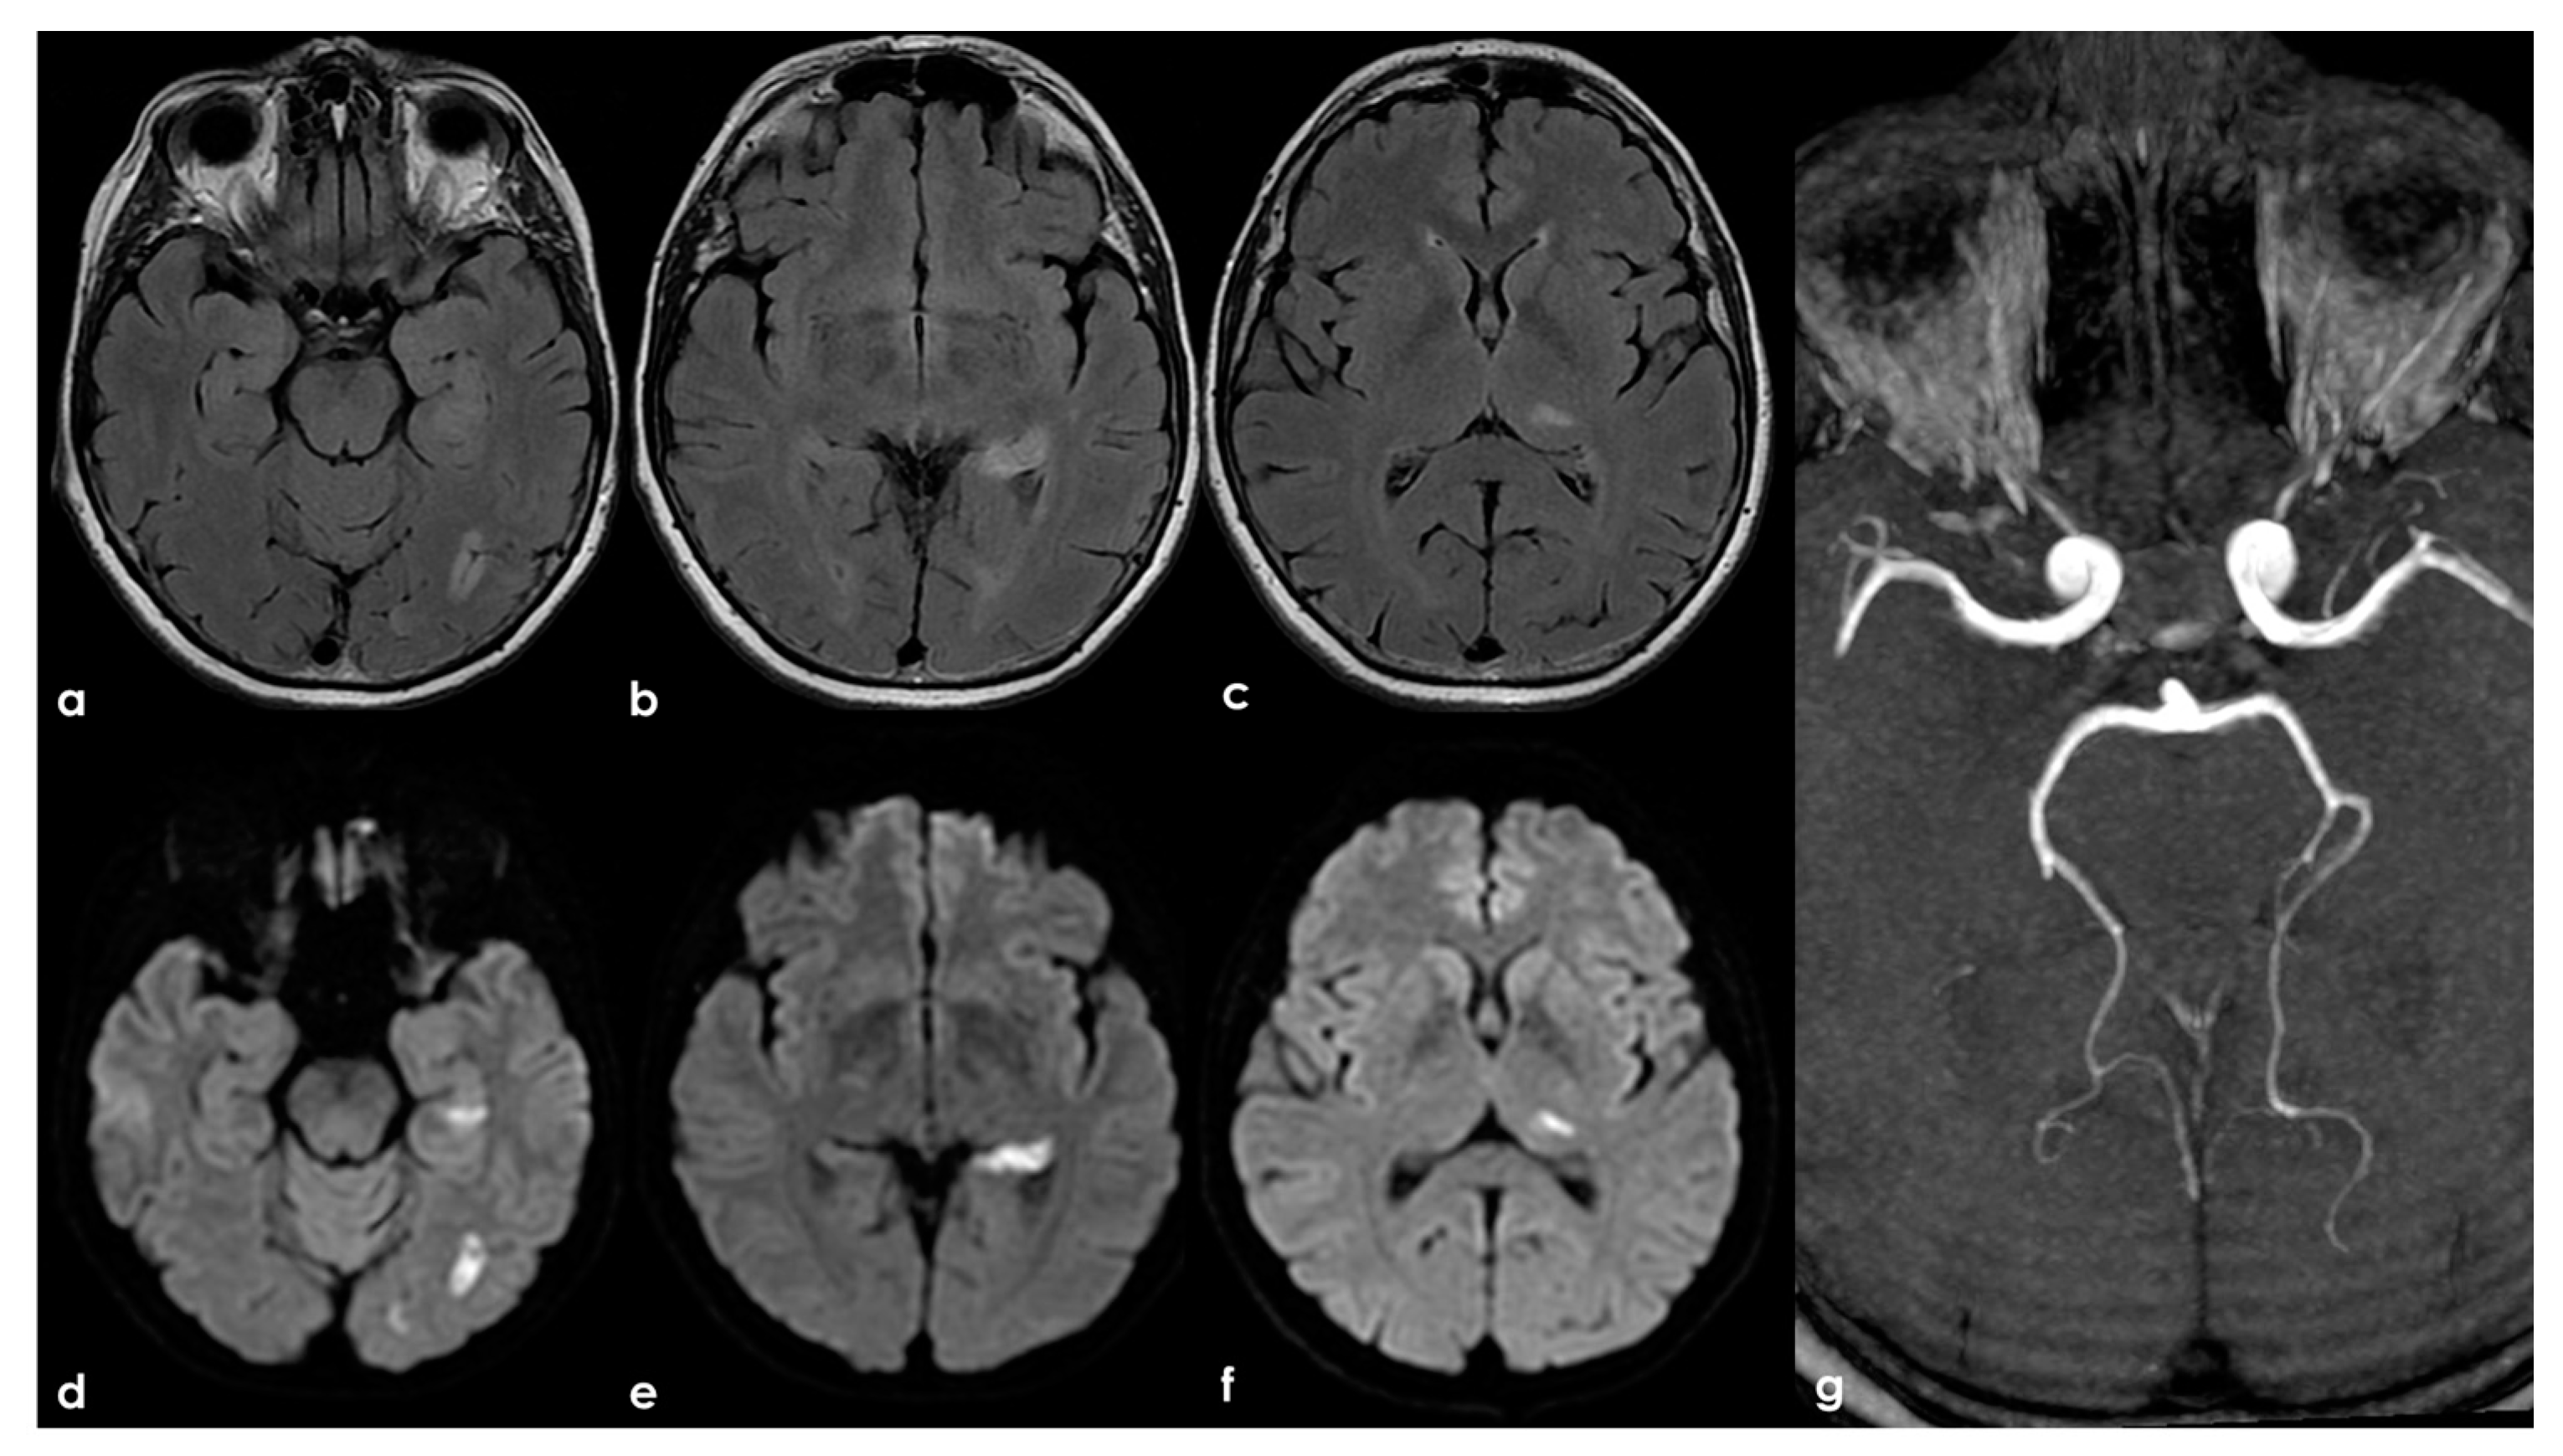

Figure 3.

A remote ischemic lesion in the right MCA territory is illustrated in the axial FLAIR sequence of the brain MRI (panel (a–c)) with the corresponding vascular imaging on a CT angiography with minimum intensity projection/multiplanar reconstruction (MIP/MPR) (panel (d,e)) in the coronal and axial plane, respectively. M1 MCA on both sides is occluded with a tiny network of small vessels partially contributing to supply M2 MCA.